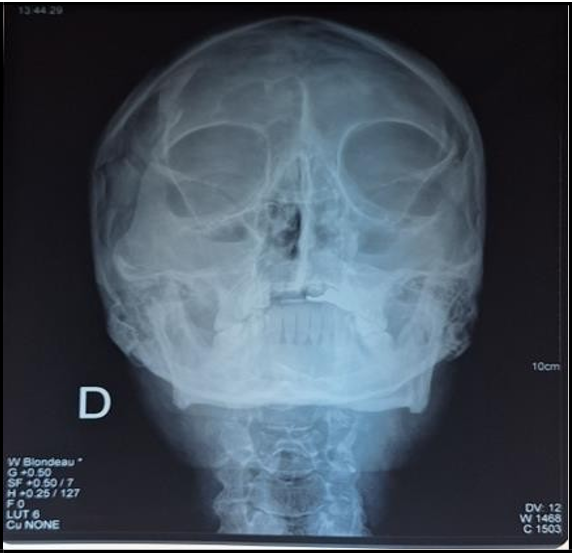

Blondeau sinus radiograph (Figure 2) shows bilateral maxillary sinusitis.

Figure 2: Sinus radiograph, Blondeau's incidence suggestive of bilateral maxillary sinusitis.